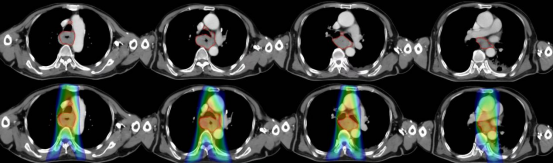

圖注:放射治療靶區(qū)及劑量分布圖,上排為治療前,可見食管癌環(huán)周病灶,食管腔變窄;紅色線包繞區(qū)為放療照射靶區(qū)。下排為放療計(jì)劃圖,可見射線照射劑量紅色高劑量區(qū)充分覆蓋靶區(qū),雙肺僅接受少量照射。

Halcyon“速銳刀”系統(tǒng)通過其高精度的圖像引導(dǎo)放療(IGRT)技術(shù),其雙層多葉光柵系統(tǒng)實(shí)現(xiàn)了射線束的零漏射和更銳利的劑量分布,進(jìn)一步降低了對肺等周圍正常組織的輻射損傷。此外,Halcyon“速銳刀”采用先進(jìn)的四維全影像引導(dǎo)技術(shù)(IGRT),在治療過程中實(shí)時(shí)獲取患者體內(nèi)腫瘤的位置和形狀信息,確保每次放療都能精準(zhǔn)命中目標(biāo)。其卓越的高速治療性能,極大地減少了老年患者的因治療時(shí)間過長造成的心理壓力。